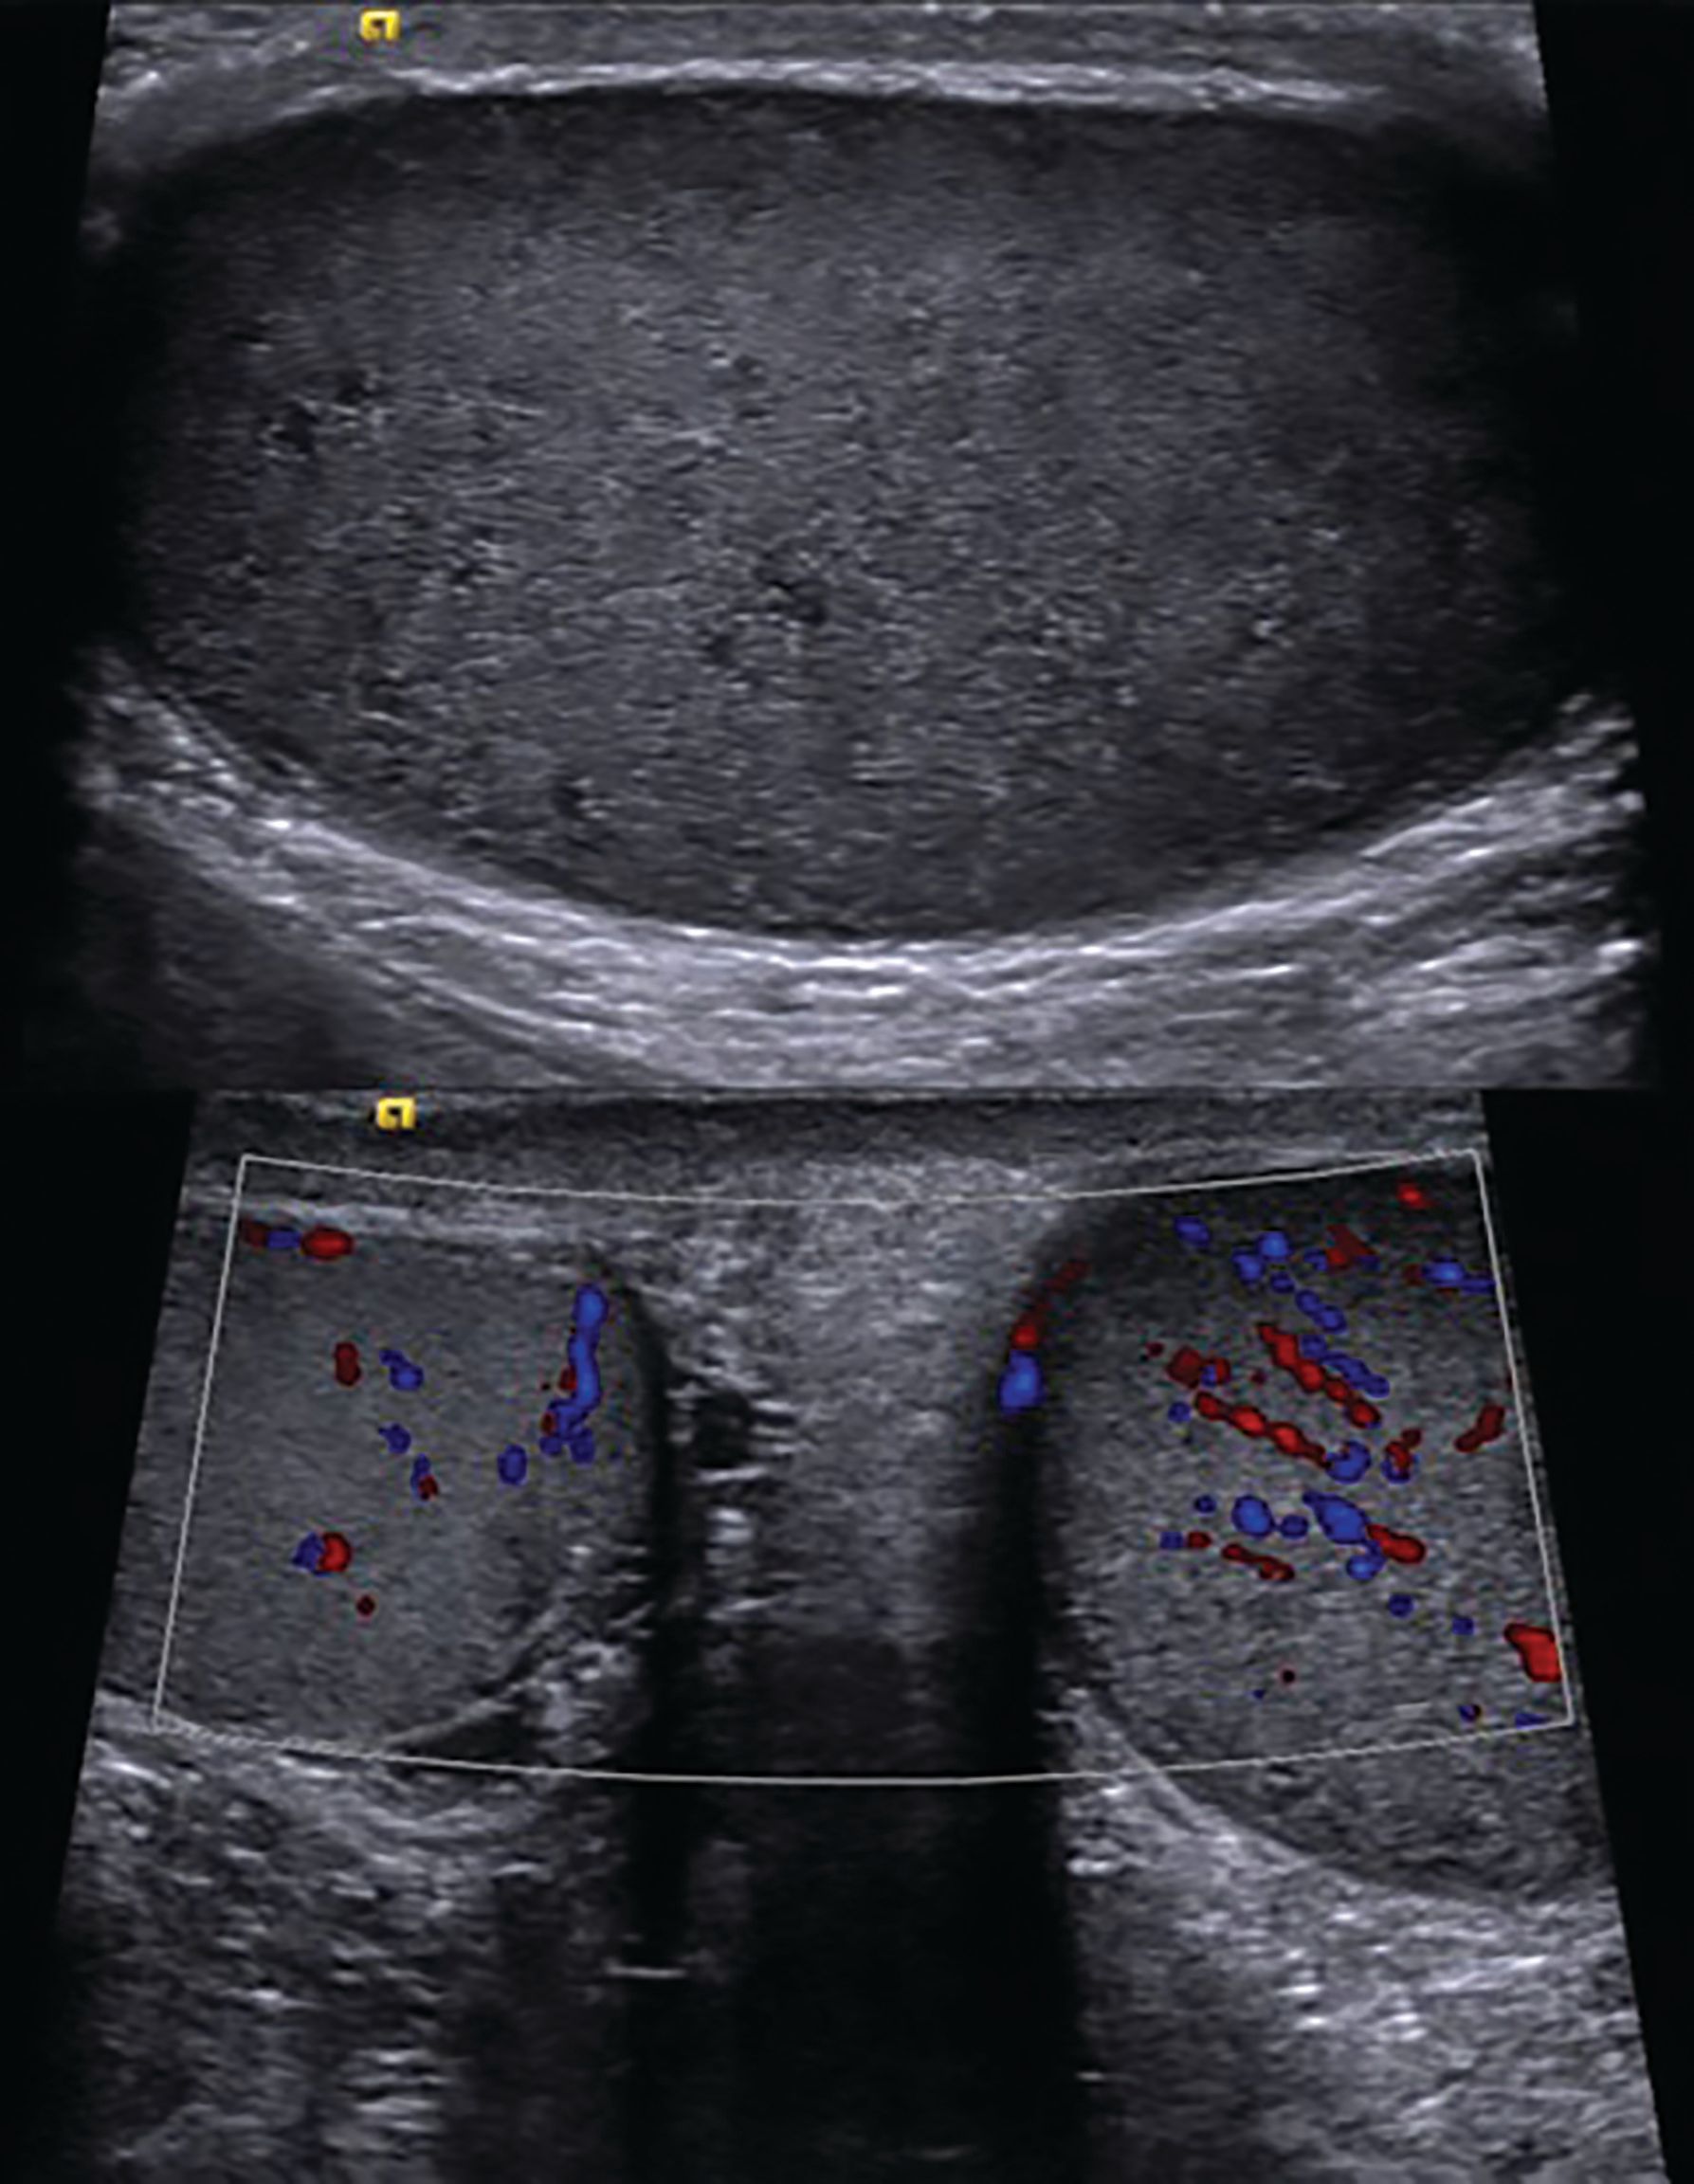

Figure 3 Ultrasound of the testes showing diffuse bilateral hypoechogenicity and increased vascularity, suggestive of leukemic infiltration.

The patient experienced remission of neurologic symptoms; however, after 5 months, he developed bilateral testicular tenderness and enlargement. An ultrasound was performed and was suggestive of leukemic infiltration (Figure 3). Chemotherapy with methotrexate and L-asparaginase in addition to radiotherapy to the testes (24 Gy in 12 fractions) was given without complications.